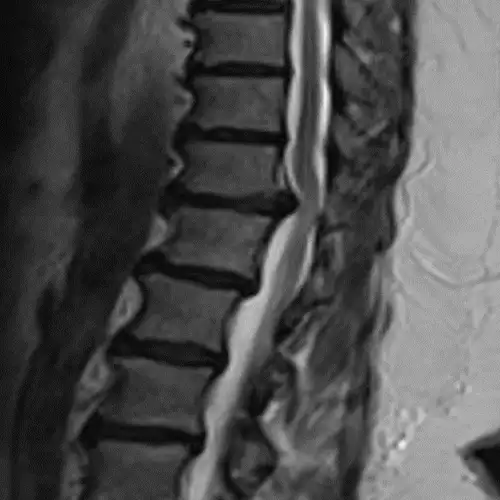

The diagnosis, in addition to being based on the symptoms and the physical examination by the specialist, is made like almost any spinal disease by means of magnetic resonance imaging (MRI), although it is usually complemented by computerized tomography (CT) and X-rays (Rx).

Sometimes contrast can be added to the intradural space in the CT and images of the spinal cord contour can be obtained (myelo-CT).